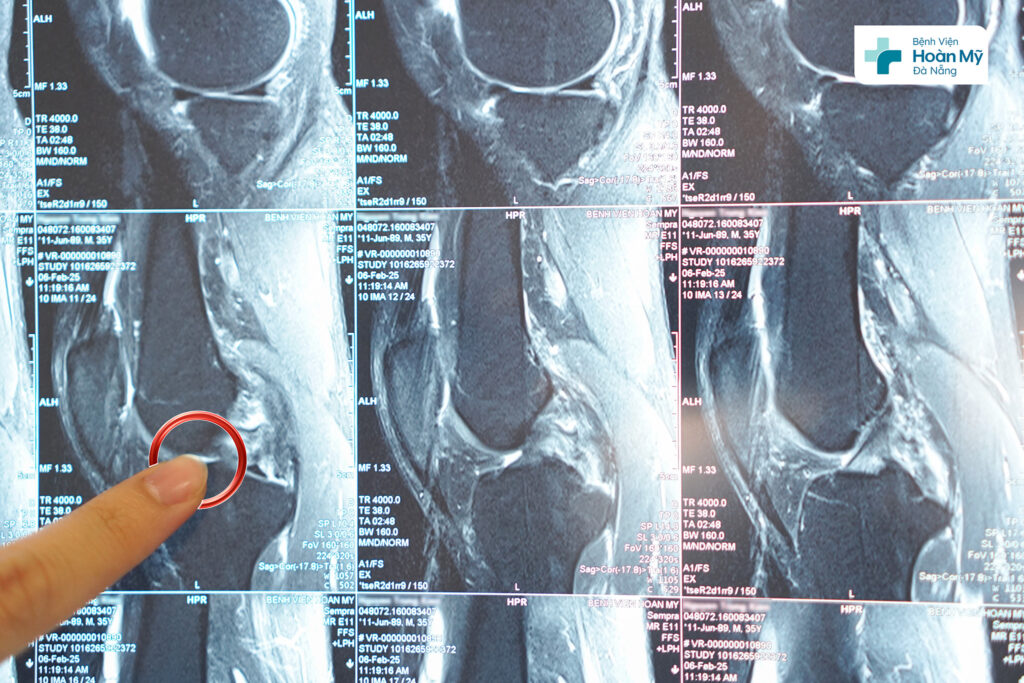

Hình ảnh dây chằng chéo sau đứt hoàn toàn trên MRI

Sau thăm khám, chụp MRI, người bệnh được chẩn đoán: đứt hoàn toàn dây chằng chéo sau gối trái. Người bệnh được thực hiện phẫu thuật nội soi tái tạo dây chằng chéo sau gối phải bằng phương pháp All INSIDE. Đây là phương pháp mới trên thế giới và được triển khai ở một số bệnh viện tuyến đầu về nội soi khớp gối ở Việt Nam. Phương pháp này cho đường mổ ít xâm lấn, thẩm mỹ, giúp người bệnh phục hồi nhanh chóng, có thể tập, vận động sớm từ đó trở lại cuộc sống bình thường sớm nhất.